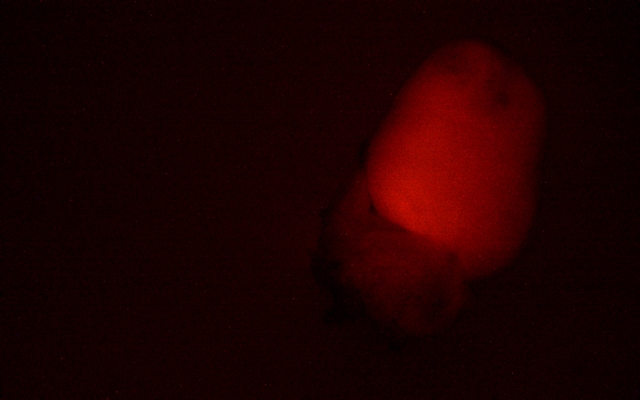

MZX81显微镜以其出色的明场和荧光成像能力,为科研人员提供了清晰锐利的观察体验。在明场模式下,心脏组织的细微结构一览无余,细胞轮廓分明,为后续的深入分析奠定了坚实基础。而切换到荧光模式时,MZX81又能够精准捕捉荧光标记信号

更值得一提的是,MZX81体视荧光显微镜拥有1:7的大变倍比,这意味着科研人员能够在不同放大倍数间自由切换,既能把握整体的心脏构造,又能深入到细胞甚至分子层面进行探索。这一特点在模式生物研究中尤为重要,它满足了科研人员对多层次、多角度观察的需求,为揭示生物体的奥秘提供了有力工具。

荧光标记小鼠心脏